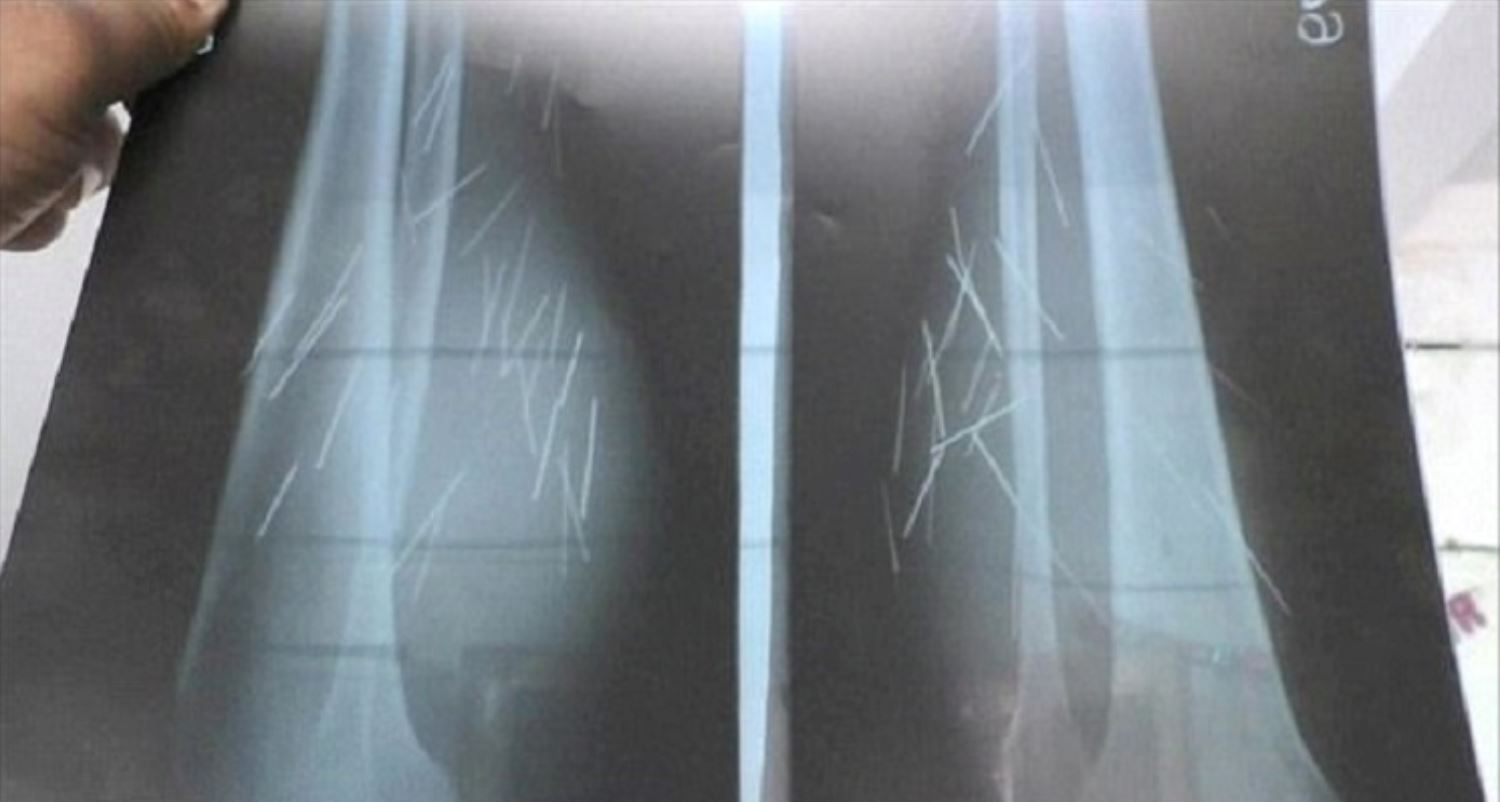

Doktor yang merawat Anusuiya, Dr Naresh Vishal, menjumpai objek-objek tajam seakan-akan jarum pada kaki wanita berkenaan selepas pemeriksaan X-ray.